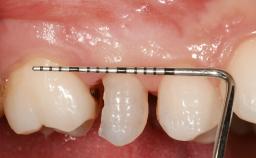

Early Placement of an Implant in a Maxillary Right Central Incisor Site

This 41-year-old female patient was referred to the clinic for the replacement of the right central incisor, since the tooth had developed a root fracture in the long axis that made extraction necessary. The healthy, non-smoking patient was first seen with the tooth still in place. A detailed Esthetic Risk Assessment was performed.The patient was worried about her dental esthetics and had high expectations for a successful treatment outcome from an esthetic point of view. The patient had a medium lip line that displayed parts of the gingiva in the anterior maxilla upon smile.

Defining Characteristics One missing tooth to be replaced by an implant-borne crown

Provisional Implant-Supported Prosthesis Prosthodontic margin < 3 mm apical to mucosal margin Prosthodontic margin < 3 mm apical to mucosal margin

Soft Tissue Contour and Volume Slightly compromised